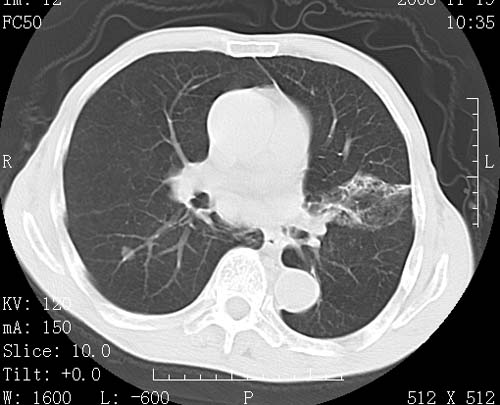

标题: CT16691:m 67 胃镜确诊食管下段及贲门癌 [打印本页]

标题: CT16691:m 67 胃镜确诊食管下段及贲门癌

术前查体,双肺部结节是转移?结核?请点评

转移 隆突下淋巴结亦肿大

首先考虑转移,纵隔内淋巴结亦肿大;

1)符合食管癌表现。2)两肺及纵隔淋巴结多发性转移瘤。3)左肺上叶舌段及两肺下叶炎症感染。

1)符合食管癌表现。2)两肺及纵隔淋巴结多发性转移瘤。3)左肺上叶舌段支气管扩张伴感染.

食管癌伴双肺转移,评述:肺部毛细血管网丰富,全身血液均快速流经肺部,癌细胞容易过滤定植,形成转移瘤,影象特点为以毛细血管末梢为中心的结节灶,边缘光滑锐利,少见有中心空洞着,不同来源的转移瘤可有各自特点,如甲状腺癌为双肺弥漫性微结节,本例有原发灶,双肺影象灶典型,左肺舌段条带状网格样伴胸膜天幕征,可视为癌性淋巴管炎。